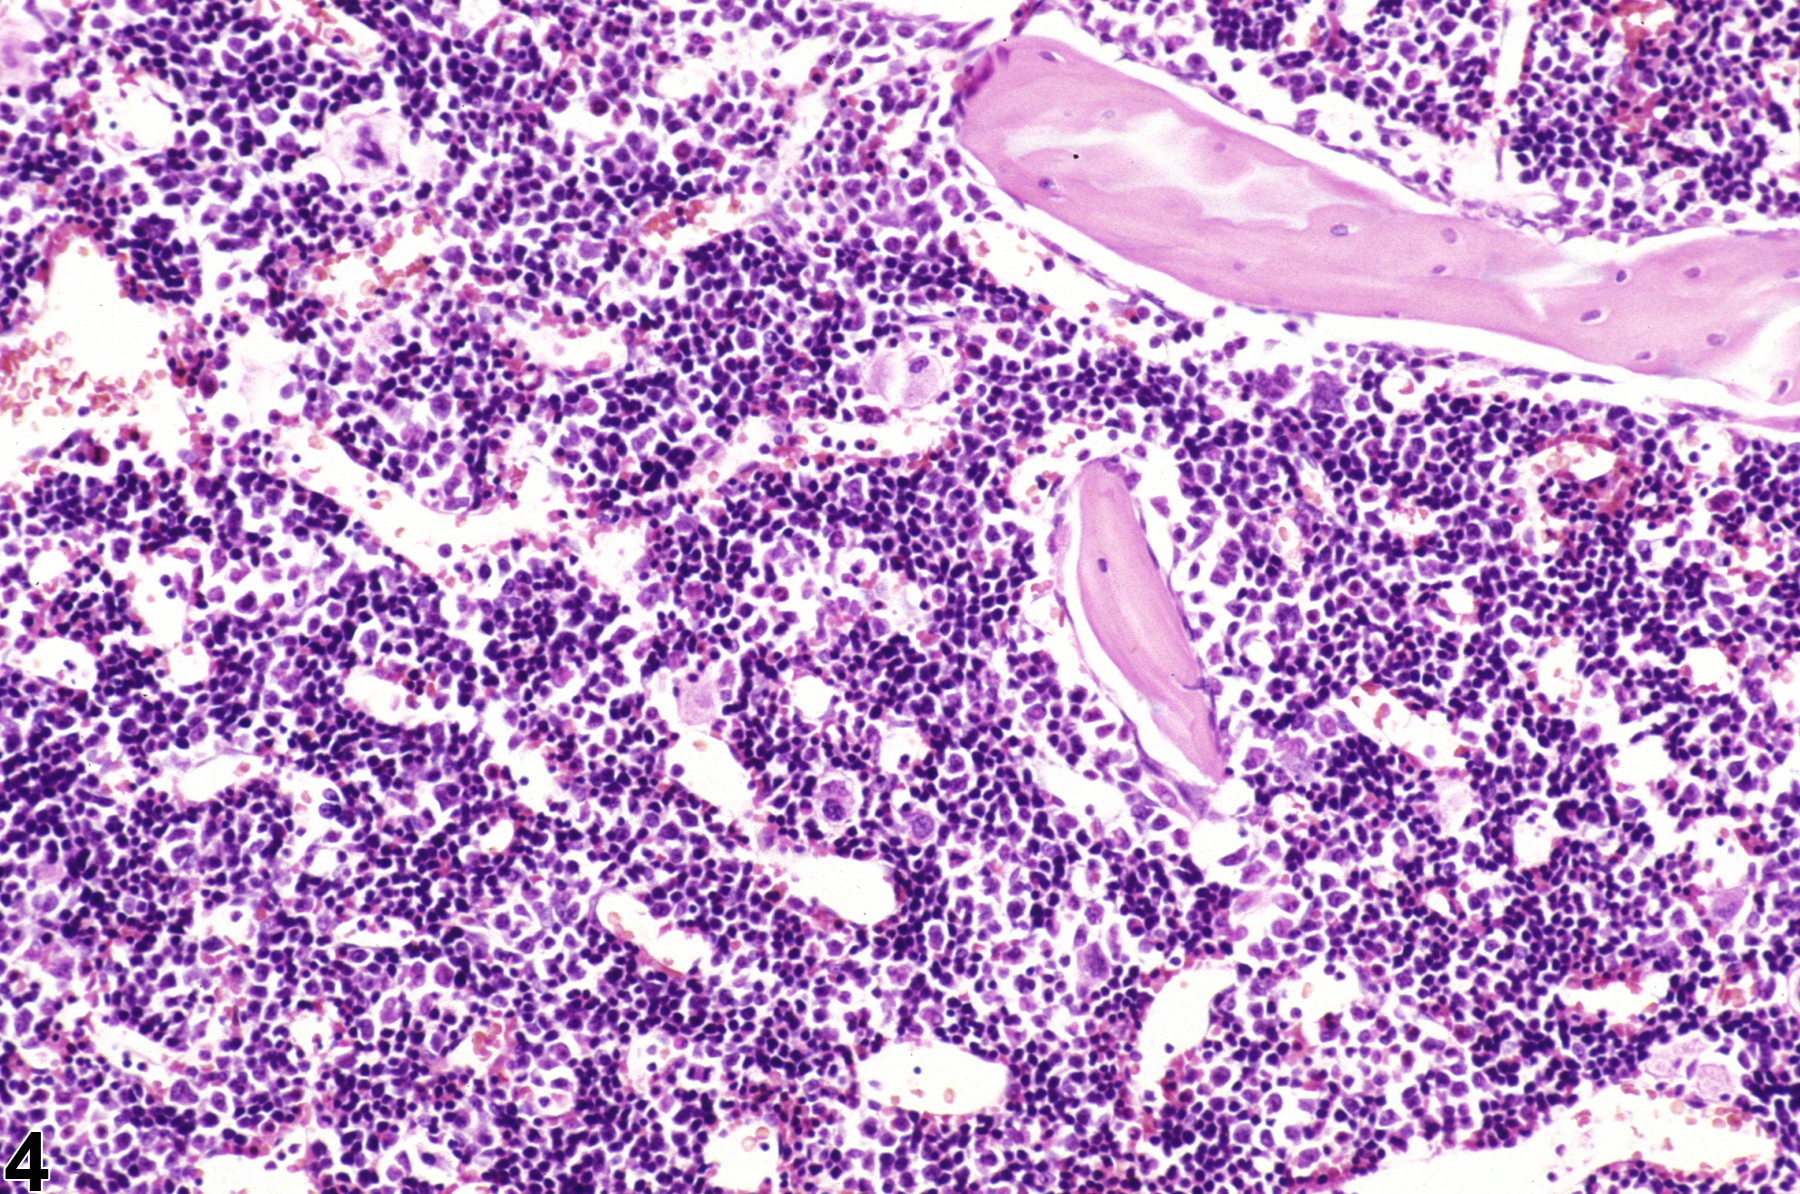

Changes in bone marrow cellularity may involve all or individual cell lines. Changes in the erythroid or myeloid cell lines may shift the M:E ratio relative to controls. Normal M:E ratios of rats and mice are reported between 0.80 and 2.79, with an average of 1.5, and are dependent on strain and age, stressing the importance of comparing treated animals with concurrent controls. Histologic sections allow for a rough estimate of the M:E ratio to aid in the evaluation of cellularity, while cytologic preparations are needed for a more precise determination of the M:E ratio and evaluation of subtle changes in synchrony of maturation.

Hypercellularity of the bone marrow is recorded in treated animals when there is an increase in hematopoietic cells relative to adipocytes compared with concurrent controls (Figure 2, Figure 4, and Figure 5). Hypercellularity may occur as a nonspecific or direct (e.g., with cytokine administration) response to compound administration but more commonly is due to a regenerative response as a consequence of decreases in peripheral blood cells, recovery from a xenobiotic-induced bone marrow injury, or inflammation. For example, hypercellularity may be secondary to sepsis or a result of blood loss, hemolytic anemia or platelet consumption/destruction. Stimulation to produce more of one cell line can cause increased production of other cell lines, causing an overall increase in bone marrow cellularity. With marked hypercellularity, hematopoietic cells may fill the entire marrow space, even extending through the nutrient foramina.

Bone marrow in a control female F344 rat from a subchronic study.